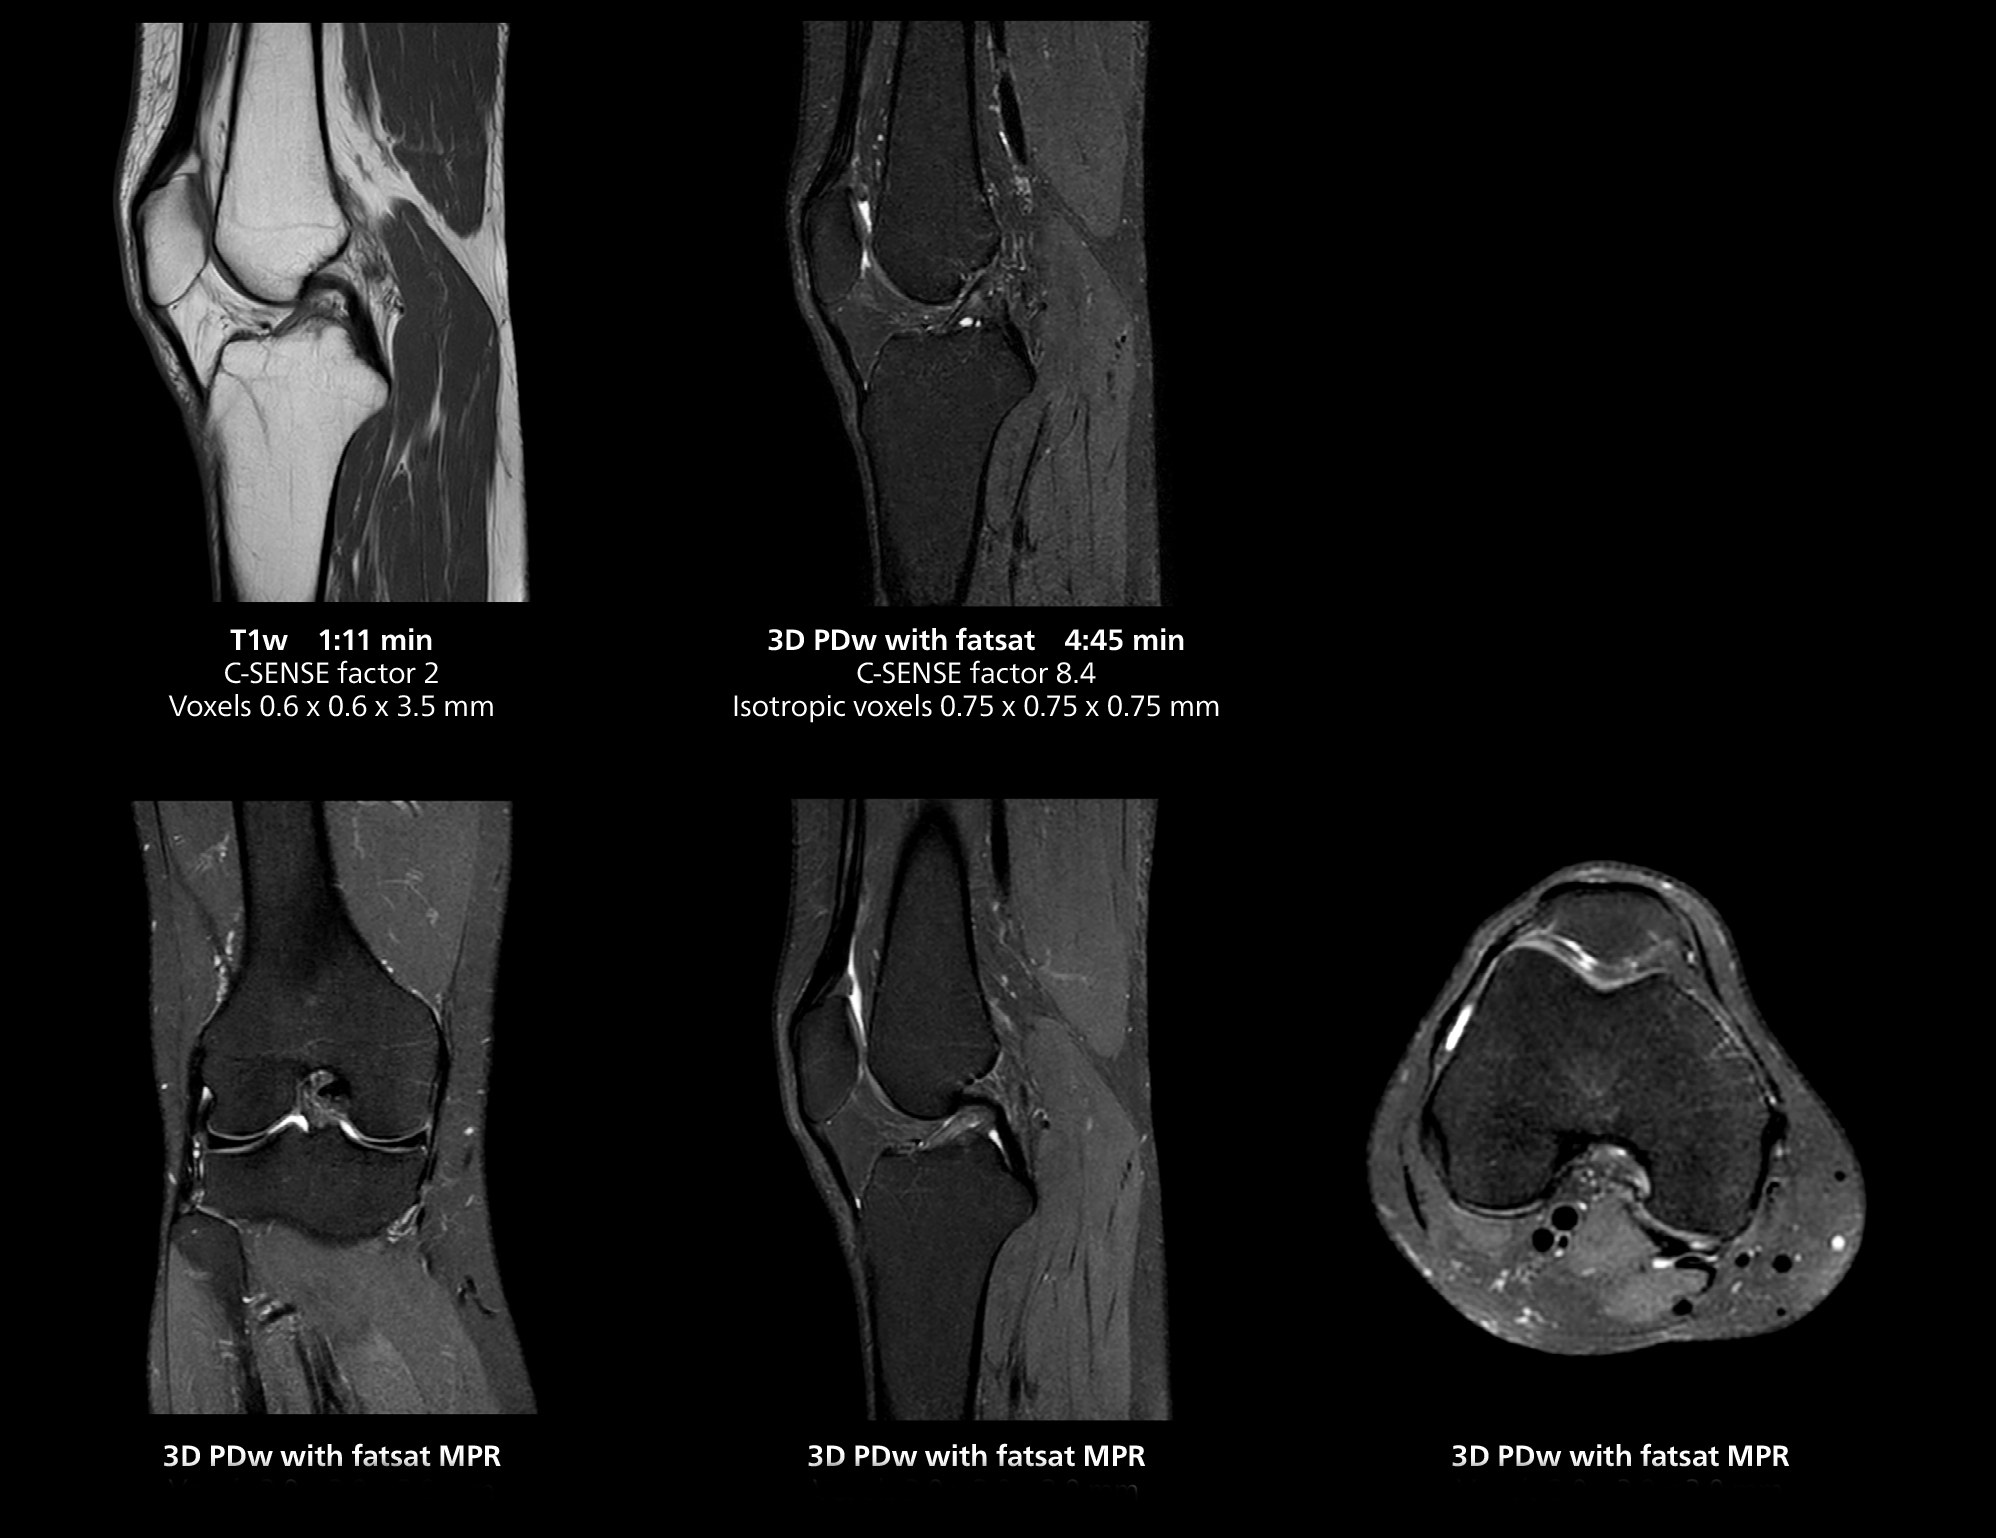

The isotropic high resolution 3D sequence in this MRI case allows for reformatting to obtain other orientations with high quality. Acquired on the MR 5300 system.

“We have more speed in 3D sequences,” Dr. Gellée states. “With Compressed SENSE, we can replace two or three 2D scans withone high-quality 3D scan. High quality additional orientations are then obtained by post-processing of the 3D data set, thus saving scanning time.”